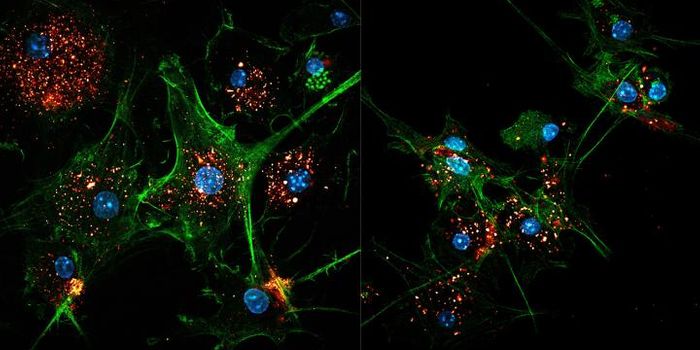

DEC 10, 2015ImmunologySuperior technology brings us novel images of cancer cells and lymphocytes this week, and now scientists can learn more ...